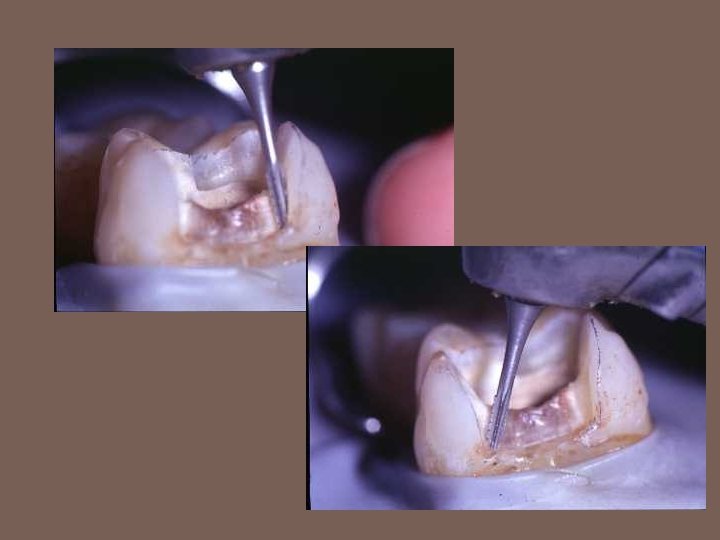

Removal of dentinal caries using round burs and spoon excavators